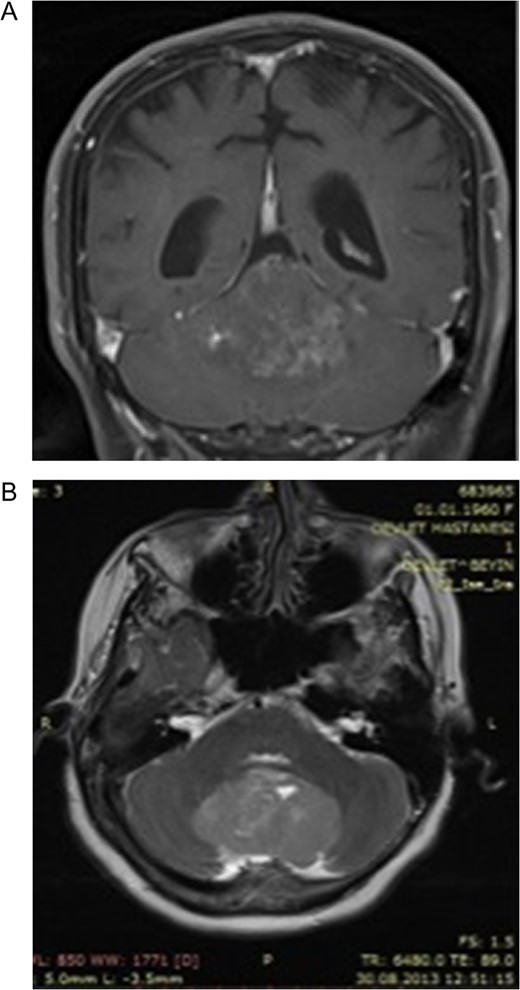

A 55-year-old woman presented with headache, dizziness and gait imbalance for 2 months. Patient’s history revealed a posterior fossa tumor that had been diagnosed 4 years ago prior to admission to our clinic. At that time, contrast enhanced of magnetic resonance imaging (MRI)showed the ill defined lesion, 5.5×3.5×4 cm in size without perilesional edema (Fig. 1A,B). During this 4 years period, her follow-up had been performed with serial MRI (Fig. 2A and B) and CT assessments (Fig. 3). Until 2 months ago, she had only intermittent headache. On neurological examination, she had cerebellar signs including ataxia and also bilateral papilledema through ocular investigations. CT assessment showed punctate calcified lesion demonstrated with undifferentiated margins of the lesion from the cerebellar parenchyma. The last MRI findings showed heterogeneous ill defined lesion without perilesional edema in vermis and extending to the adjoining cerebellar hemisphere at the supracerebellar infratentorial space with a dimension of 6.7×4×4 cm size causing compression of the fourth ventricle and marked hydrocephalous. The patient underwent surgery through a midline supracerebellar infratentorial approach in the prone position. It was a soft whitish intra-axial tumor, moderately vascular with a good plane between the vermis and cerebellum. A complete resection was achieved. The cerebrospinal fluid shunt was not decided to be placed (Fig. 4). Pathological diagnosis was reported as CLN. Immunohistochemical study, synaptophysin and neuron-specific enolase (NSE) immunopositivity were found (Fig. 5). In the mean time, glial fibrillary acidic protein (GFAP) was immunonegative and Ki-67 index was 2%. After operation, she had uneventful postoperative period and was discharged on seventh day.

(A) Post-contrast coronal T1 weighted image 4 years ago. Heterogeneous contrast enhancement of the lesion, (B) Axial-T2 weighted image showing slightly hyperintense signal of the big tumor compared with the cortex. Note that the absence of perilesional edema 4 years ago.